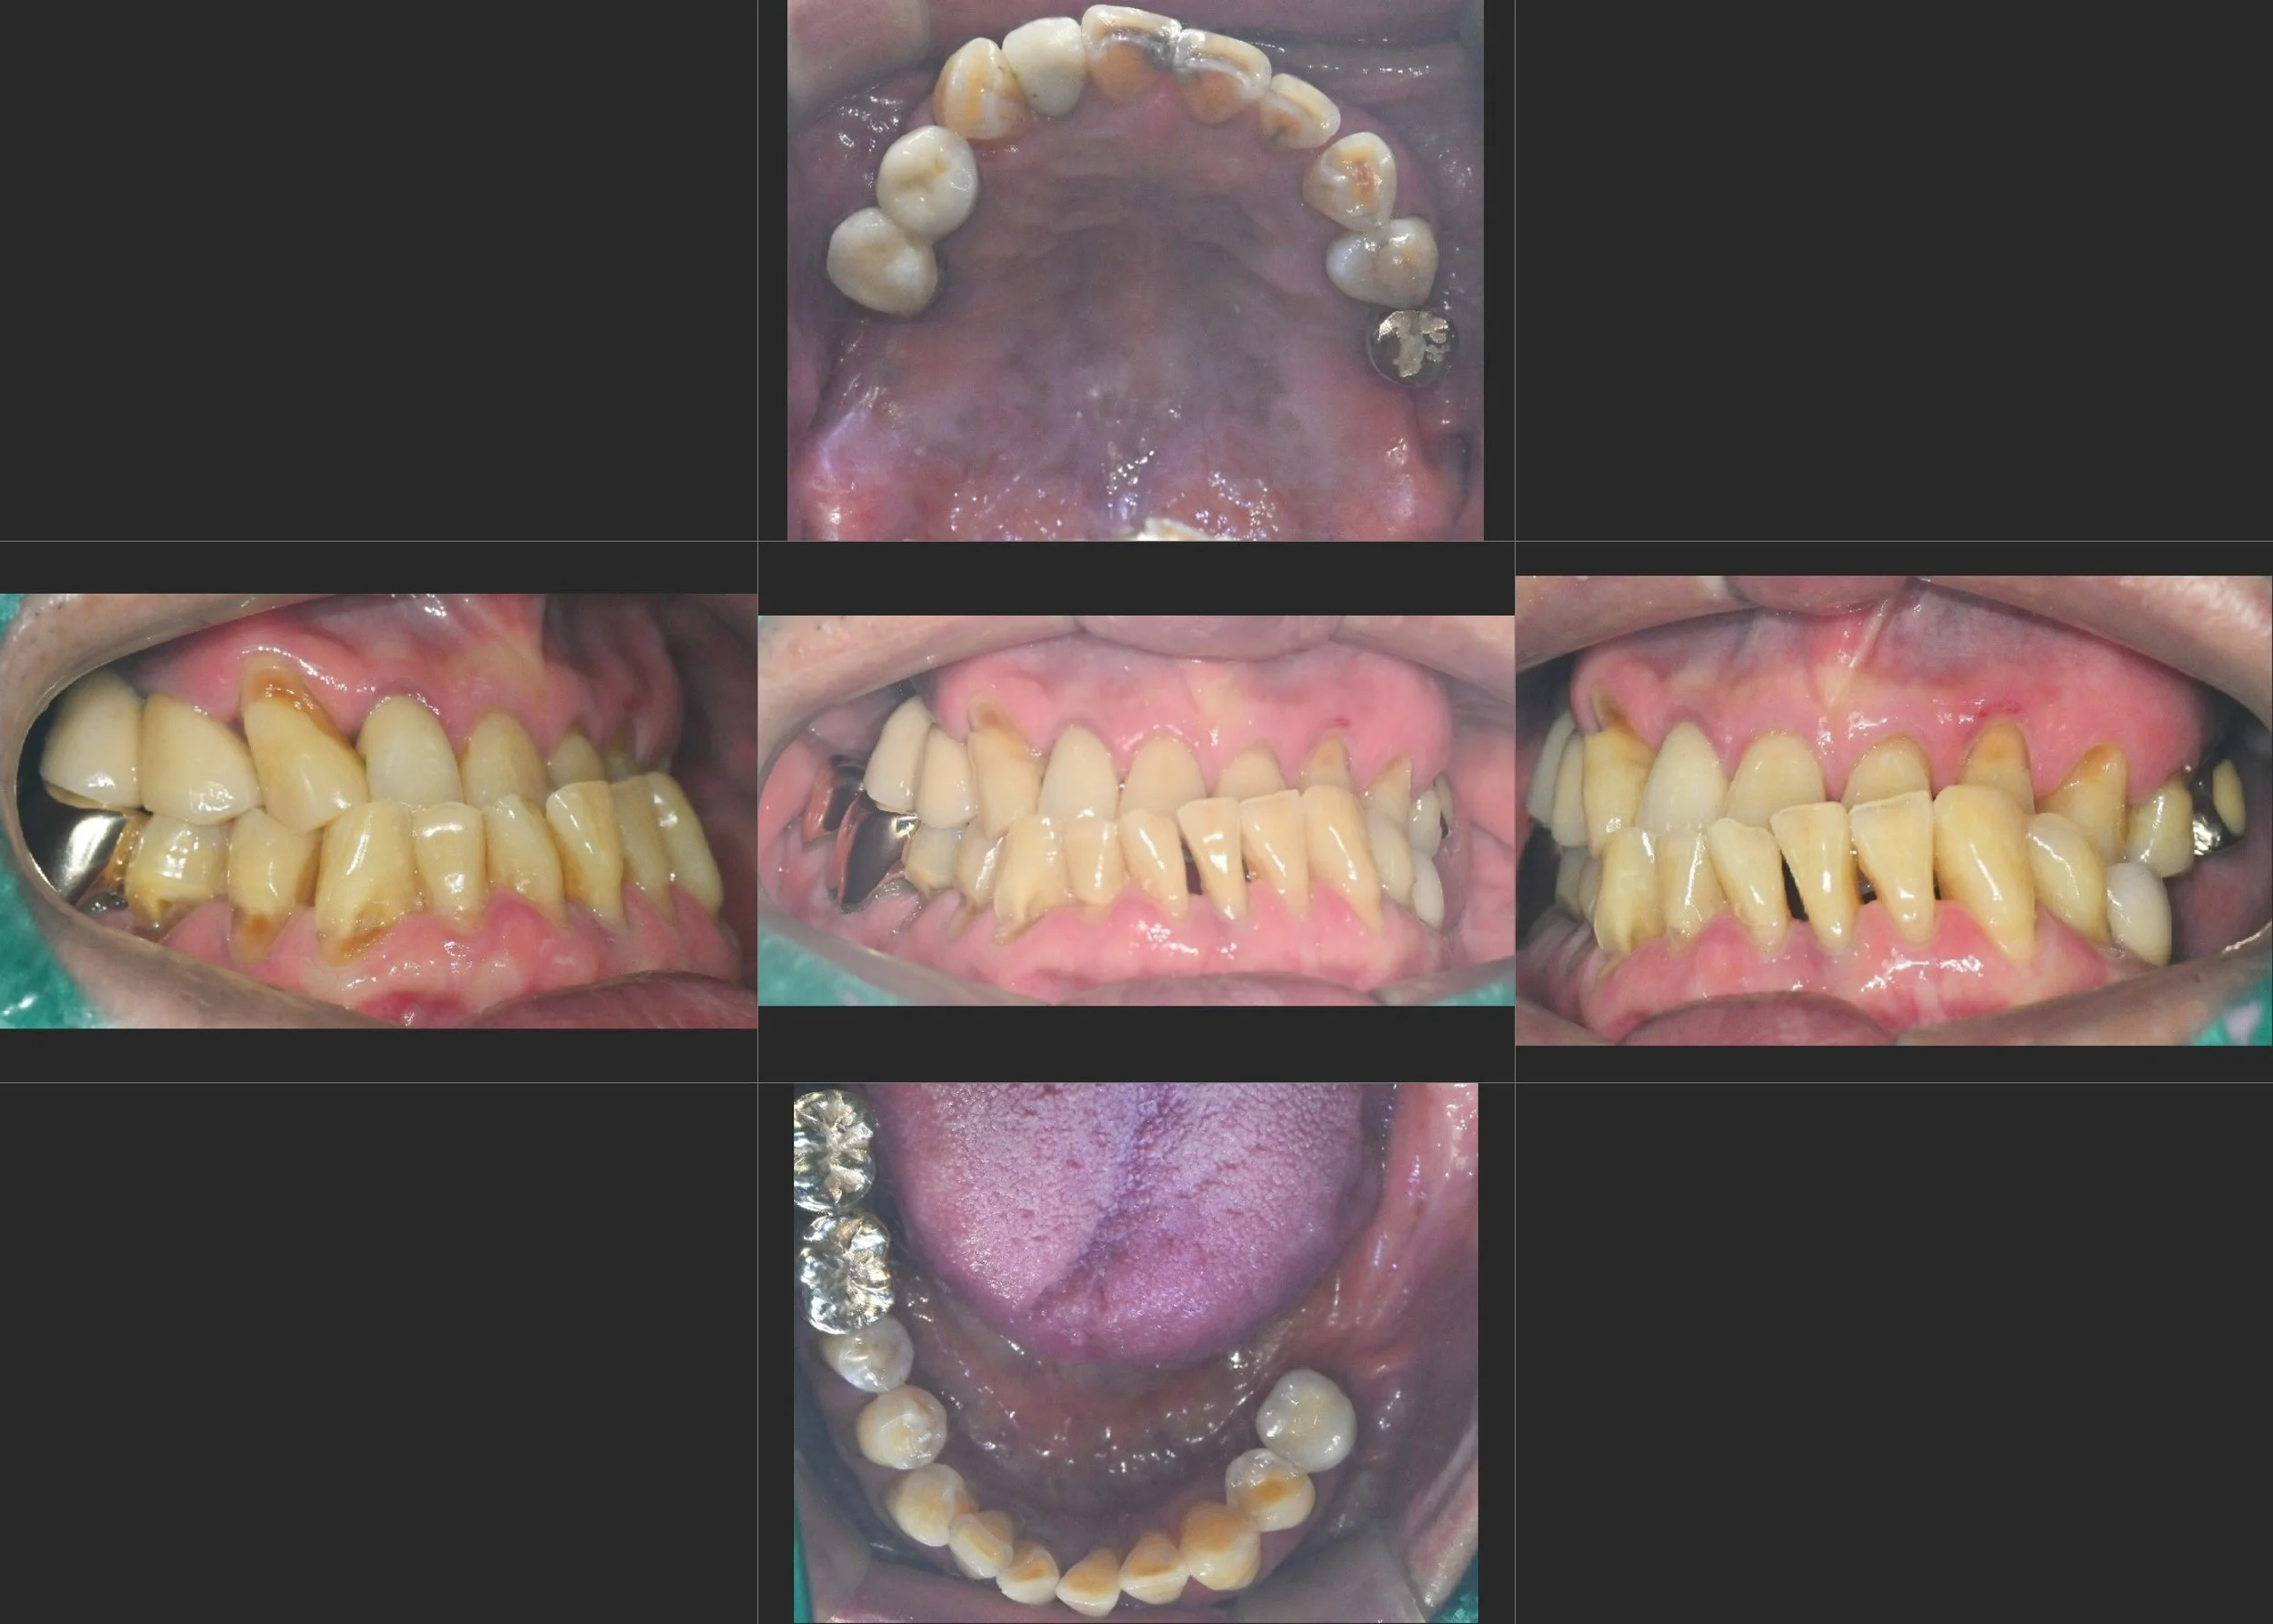

INTRA ORAL - AFTER

2. VDO Elevation & Temporary Stabilization: The most critical step was the re-establishment of a new, functional vertical dimension of occlusion (VDO). Long-term provisional restorations were utilized to stabilize the bite and guide the mandible. This process was key to non-surgically improving the functional balance and the appearance of facial asymmetry.

4. Final Prosthetic Phasing: definitivo definitive anterior porcelain bridges and crowns were delivered for aesthetic rejuvenation. Simultaneously, the final posterior implant-supported bridges were finalized at the stable VDO, ensuring a sustainable and functional result.

The final result is a transformative improvement, moving from the discomfort of iatrogenic failure and skeletal collapse to a stable, functional, and symmetrical Fixed Rehabilitation.